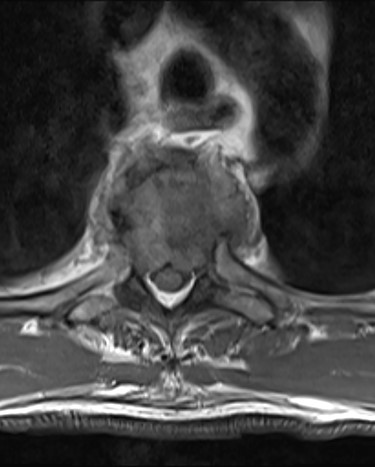

Spinal images are presented in Figs 1–6. Cross-sectional imaging revealed no other neoplastic lesion. He received dexamethasone 10 mg bolus then 4mg four times daily with appropriate proton pump inhibitor coverage. Due to no distinguishable major arterial feeder upon review of the imaging jointly with the neuroradiologist, pre-operative embolization was not attempted. The following morning, he underwent posterolateral right costotransversectomy, ligation of the ipsilateral T4 nerve root, T4 vertebrectomy and insertion of an expandable titanium cage with T1–T7 pedicle screw fixation (Figs 7 and 8). Post-operatively his pain improved to VAS 2/10 and motor power in his left lower limb improved to MRC grade 4/5. The patient was discharged home Day 10 post-admission with physiotherapy.

The patient presented with thoracic kyphosis and clinical evidence of mechanical pain. The radiological images showed evidence of three-column involvement of the T4 lytic lesion. Adjacent bilateral pedicle fracture of T5 offered no additional structural support and therefore this degree of deformity was not surprising. This spinal instability neoplastic score (SINS) [3] of 14/18 and grade 3 epidural spinal cord compression (ESCC) [2] were in support of surgical decompression and stabilization [2, 3]. A number of approaches were considered including anterior transcavitary, posterolateral extrapleural approaches and posterior decompression and instrumentation, with or without insertion of expandable titanium cage [1]. Laminectomy alone or with radiotherapy was not an option in this case as it would have offered very little decompression of this anteriorly compressing lesion as well as exacerbate the deformity by further sacrificing the posterior elements, thereby offering no contribution at structural stability.